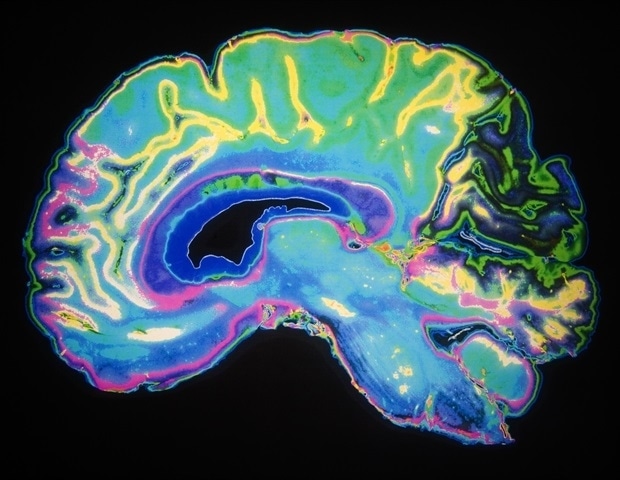

Ψυχιατρικές διαταραχές πλήττουν εκατομμύρια ανθρώπους παγκοσμίως, ωστόσο η διάγνωση τους εξακολουθεί να στηρίζεται κυρίως σε κλινικές παρατηρήσεις αντί για τυπικές βιολογικές εξετάσεις. Με αυτό το δεδομένο, επιστήμονες από την Κίνα αποφάσισαν να προχωρήσουν στην Πρωτοβουλία Υγείας Εγκεφάλου-Εντέρου (BIGHI). Πρόκειται για μια εκτενή μελέτη που συνδυάζει νευροεικόναση, ηλεκτροφυσιολογικές εξετάσεις, ανάλυση μικροβιώματος, και βιοδείκτες από το αίμα, προκειμένου να εξερευνήσει τις κύριες ψυχιατρικές διαταραχές.

Η πρόσφατη έρευνα, που περιλαμβάνει και προχωρημένες κλινικές αξιολογήσεις, έχει αναδείξει συντονισμένες αλλαγές που συνδέουν τα εντερικά μικρόβια με τα δίκτυα του εγκεφάλου και τα συμπτώματα των ψυχιατρικών διαταραχών, ενισχύοντας την ανάπτυξη της AI-assisted διάγνωσης και εξατομικευμένων θεραπειών.

Η έρευνα BIGHI, που ξεκίνησε από τους καθηγητές Fengchun Wu και Yuanyuan Huang από το Τμήμα Ψυχιατρικής του Νοσοκομείου Εγκεφάλου Guangzhou Medical University, περιλαμβάνει περισσότερους από 1,200 συμμετέχοντες ηλικίας 18-45 ετών. Οι συμμετέχοντες υποβάλλονται σε πολλαπλές αξιολογήσεις, περιλαμβάνοντας κλινικές αξιολογήσεις, νευρογνωστικές δοκιμές και αξονική απεικόνιση.

Η μελέτη προσφέρει επιπλέον δέσμες δεδομένων σχετικά με τις αλλοιώσεις της δομής του εγκεφάλου κατά τη διάρκεια των διάφορων ψυχιατρικών καταστάσεων. Με τη χρήση μοντέλων μηχανικής μάθησης στις MRI εξετάσεις, παρατηρήθηκε υψηλή ακρίβεια στην κατηγοριοποίηση ασθενών με σχιζοφρένεια και την αναγνώριση συνδετικών προτύπων που σχετίζονται με αυτοκτονικές σκέψεις στη διπολική διαταραχή και τις επιπτώσεις του παιδικού τραύματος στην κατάθλιψη.